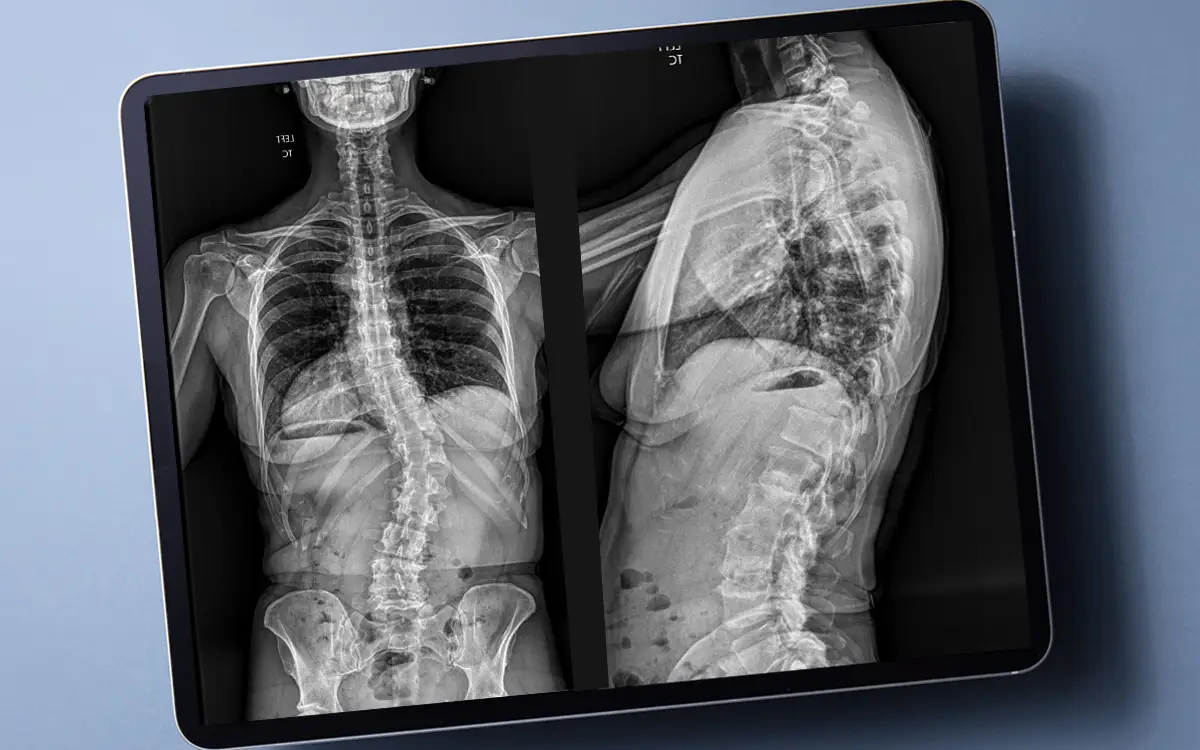

Scripps has long been at the forefront of innovation, and has now adopted

advanced technology that is redefining what is possible in spinal care. Scripps

spine surgeons are using an imaging system called EOSedge to help diagnosis and

treat spine conditions. The device captures high quality, full-body images in just

seconds with significantly reduced radiation exposure. Its use has allowed

Scripps physicians to think big and continue to lead the way in improving spinal

care. Click here to read more about this imaging game-changer.